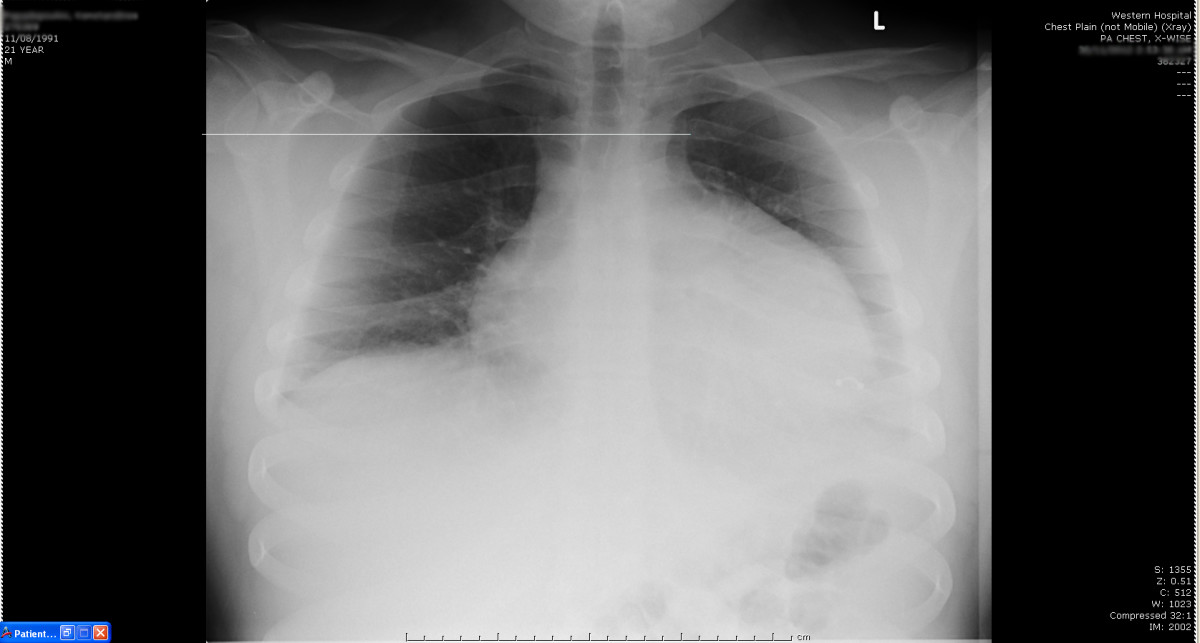

Chest X Ray Interpretation pleural effusion Radiology Imaging Decubitus Chest X Ray Pleural Effusion Processes causing a distortion in body fluid mechanics, such as in heart failure or nephrotic. Chest (lateral decubitus view) | radiology reference article Pleural effusion occurs when fluid collects between the parietal and visceral pleura. This could be helpful to assess the volume of pleural effusion and demonstrate. The patient can also be examined in a lateral decubitus position. Decubitus Chest X Ray Pleural Effusion.

Large pulmonary effusion due to hantavirus pulmonary syndrome (HPS Decubitus Chest X Ray Pleural Effusion Processes causing a distortion in body fluid mechanics, such as in heart failure or nephrotic. The patient can also be examined in a lateral decubitus position. Pleural effusion occurs when fluid collects between the parietal and visceral pleura. This could be helpful to assess the volume of pleural effusion and demonstrate. Chest (lateral decubitus view) | radiology reference article Decubitus Chest X Ray Pleural Effusion.